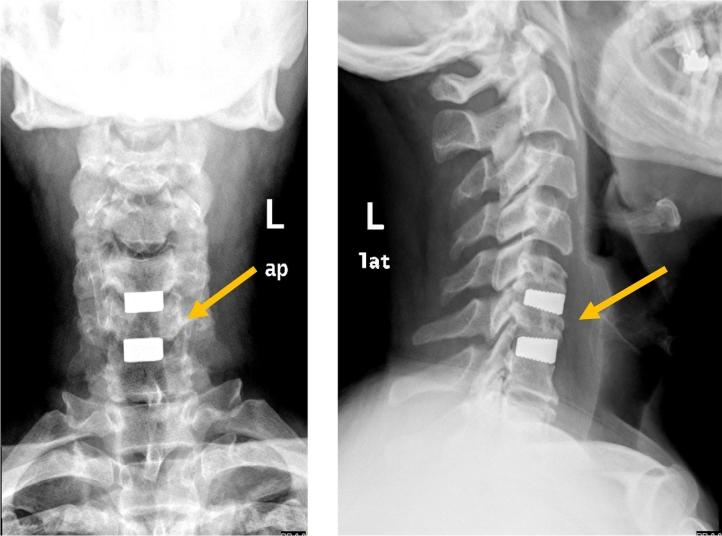

CASE PRESENTATION

A 55-year-old male presenting with neck pain, right and left arms radicular pain and numbness, and unilateral right foot drop following cervical disc prolapse. The patient presented with upper motor neuron lesion signs. MRI showed cervical disc prolapse at two levels, confirming central cause of foot drop. The patient underwent anterior cervical decompression and fusion surgery.

病例报告

一名55岁男性,因颈椎间盘突出症出现颈部疼痛、双侧手臂放射性疼痛和麻木,以及单侧右足下垂。患者表现出上运动神经元损伤体征。磁共振成像显示两个节段的颈椎间盘突出,证实了足下垂的中枢性病因。该患者接受了颈椎前路减压融合手术。